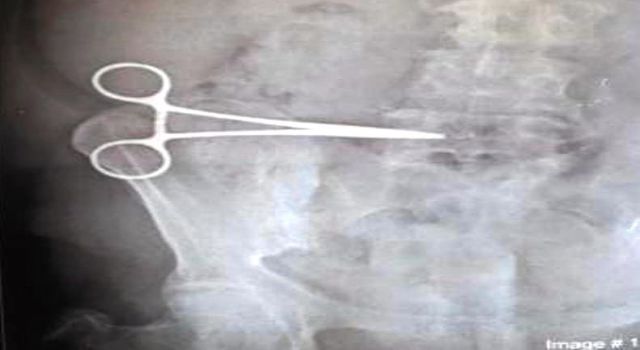

Aydın’ın Kuşadası ilçesinde yaşayan Nurcihan Öğmen'in (65), mide şikayeti nedeniyle özel bir hastanede geçirdiği operasyon sırasında karnında makas unutuldu. Ameliyattan sonra ağrıları dineceğine daha da artan Öğmen, daha sonra gittiği Söke Devlet Hastanesi’nde yapılan incelemede karnında makas unutulduğunu 2 ay sonra öğrendi. Özel hastanedeki ameliyat ekibinin Nurcihan Öğmen'in karnında unuttuğu makas Söke Devlet Hastanesi'nde yapılan ikinci bir ameliyatla alındı.

Edinilen bilgiye göre; Kuşadası’nda yaşayan Nurcihan Öğmen (65), 5 Mart 2021’de Kuşadası'ndaki özel bir hastanede mide rahatsızlığı nedeniyle operasyon geçirdi. Hastanede yapılan ameliyattan bir gün sonra taburcu edilen Öğmen’in ağrıları hiç dinmedi. Durumu doktoruna bildiren Öğmen buradan sonuç alamayınca 3 Mayıs 2021’de Söke Devlet Hastanesi’ne müracaat etti. Burada hastaya çekilen röntgeni inceleyen doktorlar gözlerine inanamadı. Hastanın 2 aydır karnında unutulan makas ile yaşadığını fark eden doktorlar Nurcihan Öğmen'i ameliyata alarak kadının karnında unutulan makası çıkardı.